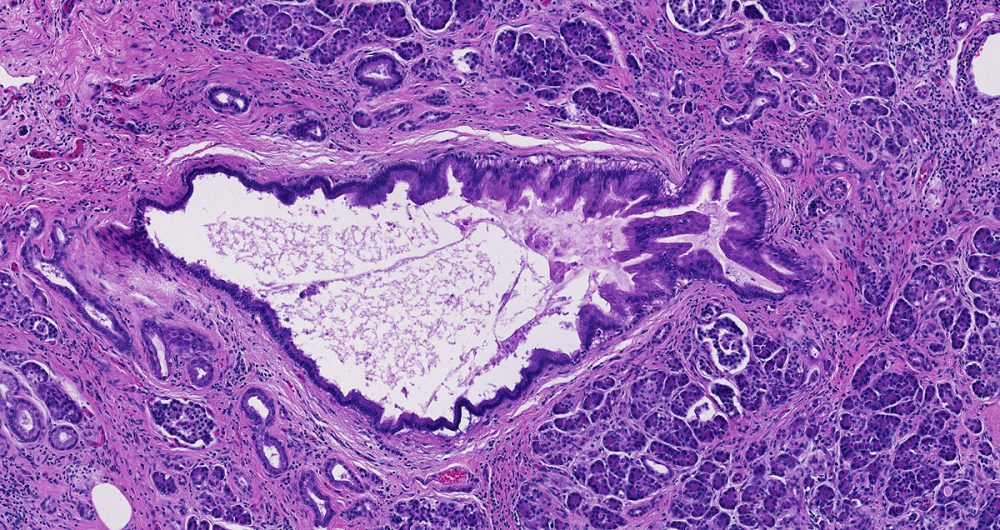

Low-grade pancreatic intraepithelial neoplasia encompasses three older terms- PanIN-1A, PanIN-1B and PanIN-2.